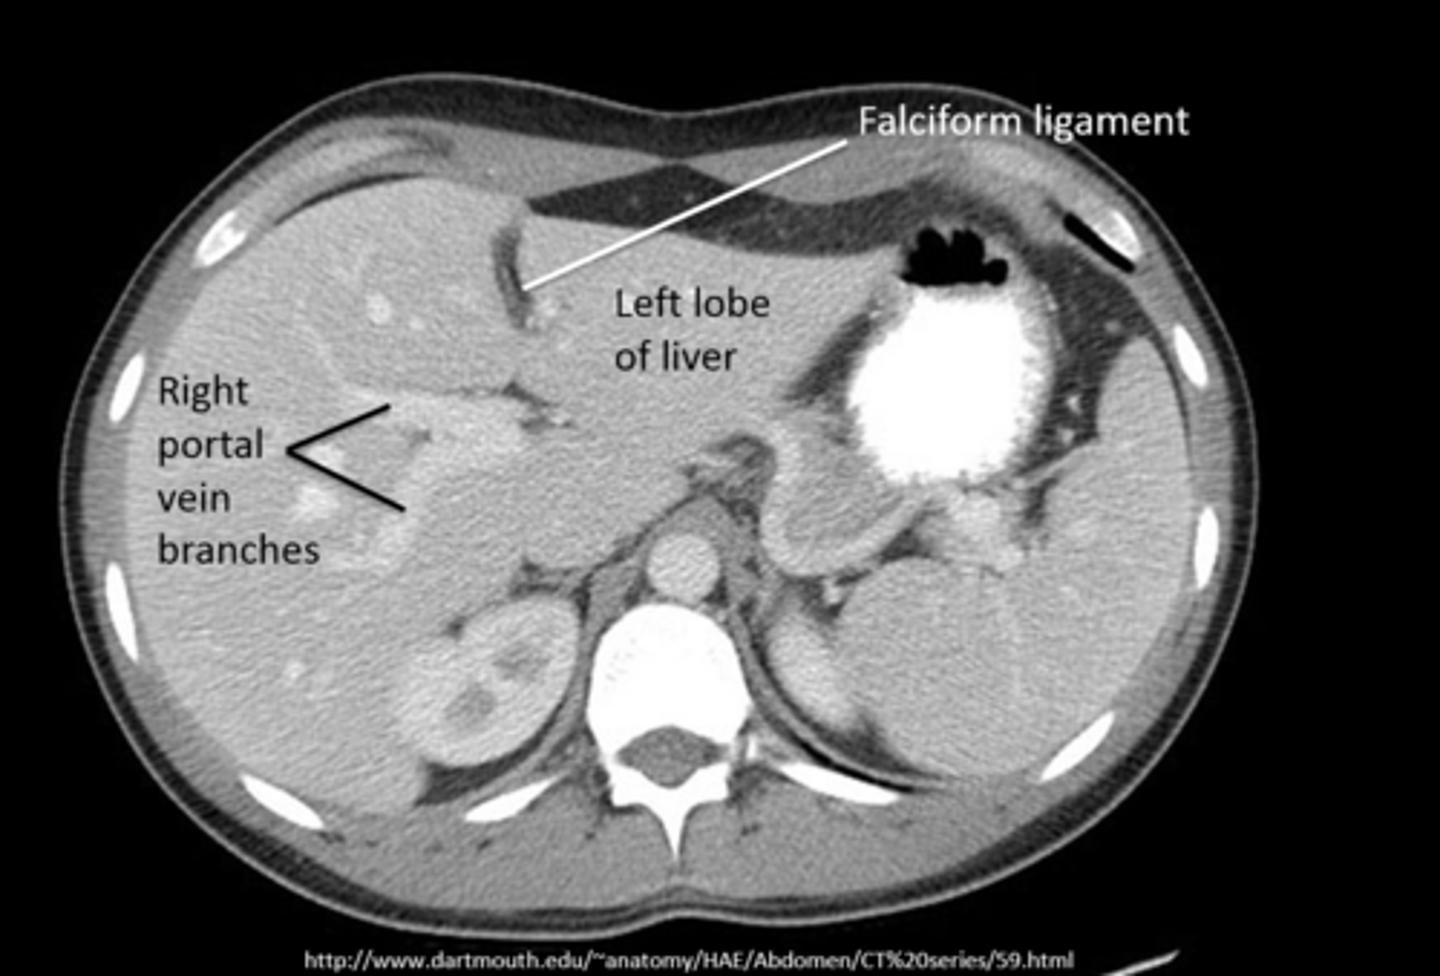

intraperitoneal air (pneumoperitoneum)

air in peritoneal cavity, caused by rupture of an air-containing loop of bowel, trauma, or abdominal surgery (5-7 days post op)

1. air beneath diaphragm

2. rigler sign- visualization of both sides of bowel wall

3. visualization of falciform ligament